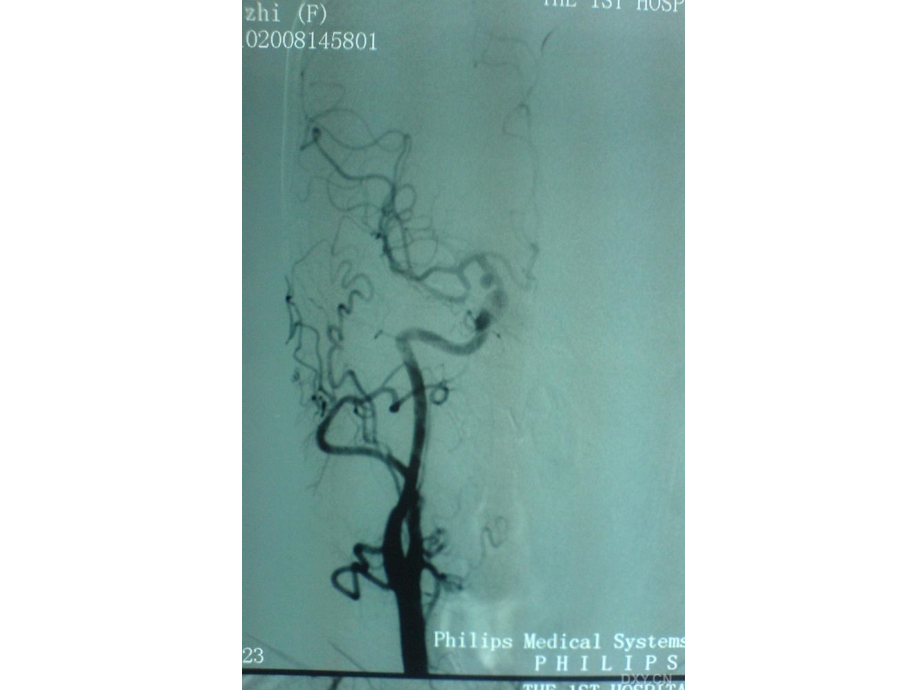

单击此处编辑母版标题样式,单击此处编辑母版文本样式,第二级,第三级,第四级,第五级,*,*,*,罗某某 女 53岁 头痛5天,呕吐半天与18:19入院自诉五天前开始觉头痛,头痛渐渐加重,今日早晨6时许患者在睡眠中突发呕吐涎水,右眉弓处疼痛,入院前共呕吐了约8次,入院时仍觉右眼部胀痛,右眉弓明显,视物模糊,入院体查见:右眼睑下垂,右侧瞳孔约4mm,对光反射消失,右眼球向下、向上、向内运动受限,右侧调节反射消失,左侧眼球未见异常,口角无歪斜,伸舌居中,颈软无抵抗,肌力肌张力健反射未见异常,辅助检查:颅CT平扫未见明显异常,颅CT骨窗未见明显占位,另外患者有蛛网膜下腔出血史,未遗留明显后遗症。,fbls053243,后交通动脉瘤啊!很明显的,SAH也是它引起的,它是导致动眼神经麻痹比较常见的原因之一,Jmoren,考虑后交通动脉瘤。如图所示,考虑后交通动脉瘤。如图所示,